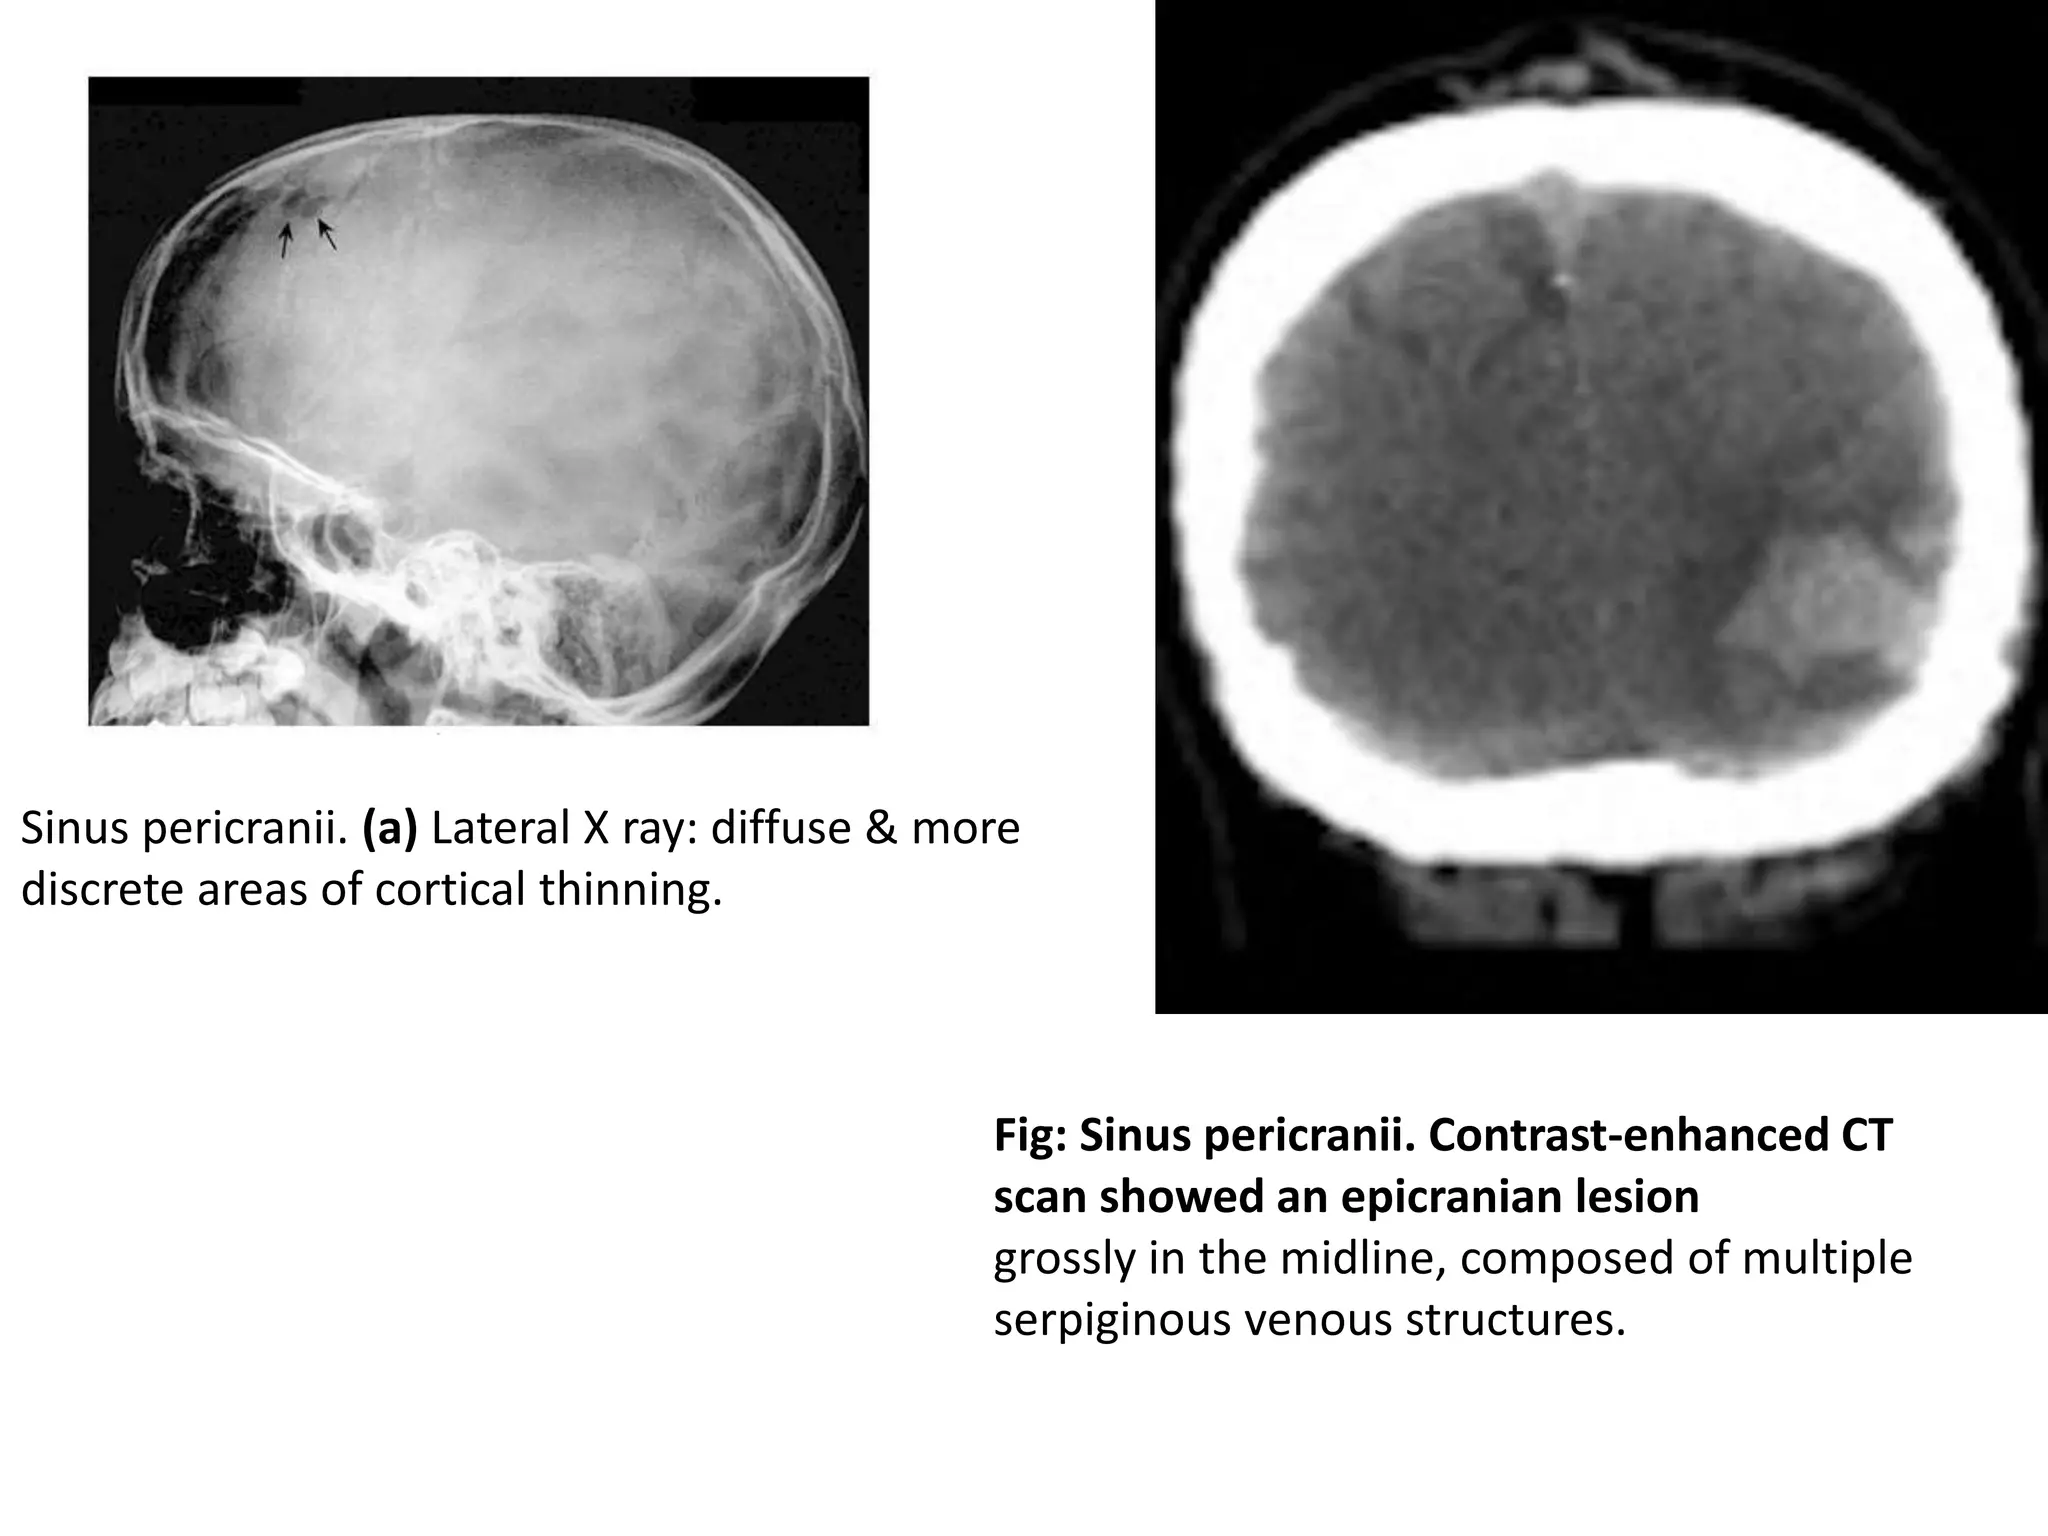

Sinus Pericranii

• Abnormal communication between the intracranial and

extracranial venous drainages, usually congenital.

• manifesting as a fluctuating mass in the scalp, which varies

in size according to intracranial pressure changes.

• Ultrasound evaluation provides an accurate diagnosis .

However, contrast-enhanced CT is a more popular method,

showing an enhancing epicranial mass composed of

serpiginous vessels.

• Although complication by thrombosis has been described,

treatment has basically been recommended for aesthetic

reasons.

• Preoperative endovascular embolization is a promising

technique on preventing haemorrhage.

Fig: Sinus pericranii. Contrast-enhanced CT

scan showed an epicranian lesion

grossly in the midline, composed of multiple

serpiginous venous structures.

Sinus pericranii. (a) Lateral X ray: diffuse & more

discrete areas of cortical thinning.